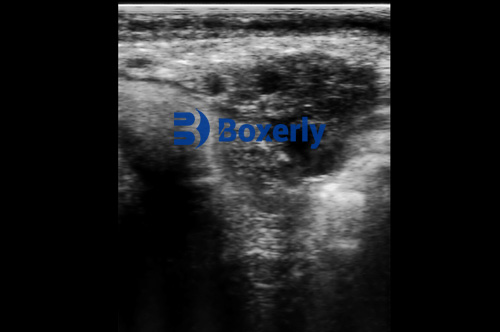

Veterinary ultrasound is a diagnostic imaging technique that uses high-frequency sound waves to create real-time images of an animal’s internal organs and tissues. Unlike X-rays, which use radiation, ultrasound is completely safe and painless. It allows veterinarians to examine the heart, liver, kidneys, bladder, and other organs without the need for surgery. This makes it an invaluable tool for detecting issues like tumors, cysts, pregnancy, and even foreign objects swallowed by pets.

During an ultrasound examination, a small handheld device called a transducer is moved over the animal’s body. The transducer emits sound waves that bounce off internal structures and return as echoes. These echoes are then converted into images displayed on a monitor. The procedure is quick, usually taking 20 to 30 minutes, and most pets tolerate it well without sedation. For larger animals, specialized equipment like those from BXL, a manufacturer of large animal ultrasound devices, ensures accurate imaging even for horses or livestock.